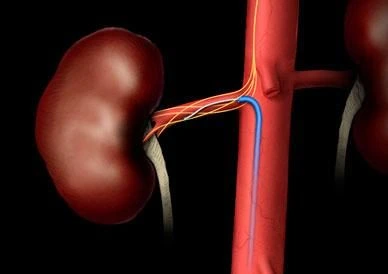

La procedura consiste nell’inserimento di un catetere del tutto simile a quello utilizzato per la

vascolarizzazione cardiaca che viene fatto avanzare fino alle arterie renali. Una volta

posizionato, il catetere lancia un segnale in radiofrequenza, in grado di distruggere le fibre

nervose dell’arteria del sistema simpatico renale e inibirne quindi l’attività consentendo una

riduzione significativa dei valori pressori.